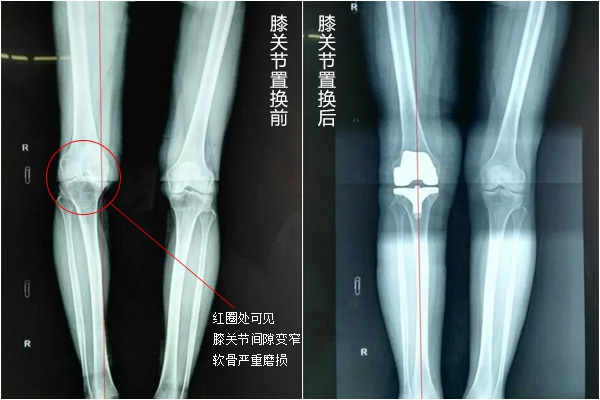

全膝关节置换术(Total KneeArthroplasty,TKA)是一种治疗骨关节炎的有效方法,切除机体已无法自行修复的关节面,用人工关节部件代替损坏的关节,矫正下肢力线,解除膝关节疼痛,改善膝关节功能,维持关节稳定性的一种治疗方法。膝关节置换的目的是各种原因导致的关节结构发生改变,如果单纯使用药物治疗只能缓解疼痛症状,而不能改变关节结构的变化,而人工关节置换的目的就是缓解疼痛、稳定关节、矫正畸形,如 “罗圈腿”、“X”腿、改善关节功能,使原先僵硬活动受限的关节能够活动,功能得到极大的改善。

人工膝关节置换术就是将已磨损破坏的关节面切除,再换上一个人工的关节面”,可以将它比作给坏牙安装了一副“牙套”。这副“牙套”采用金属、高分子聚乙烯、陶瓷等材料制作而成,根据人体关节的形态、构造及功能制成人工关节假体通过外科技术植入人体内,代替患病关节的功能,达到缓解关节疼痛,恢复关节功能的目的。